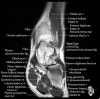

- Coronal section

The coronal oblique T1 sequence follows the tendons of the ankle around the malleolar turns and also evaluates the medial ankle ligaments.

The coronal oblique PD fat suppressed sequence follows the tendons of the ankle around the malleolar turns and is particularly important in evaluation of the Posterior tibialis tendon.

Bone and marrow

Talar dome

Deltoid ligament

Tendons in arch

Plantar fascia

Troubleshoot ligaments